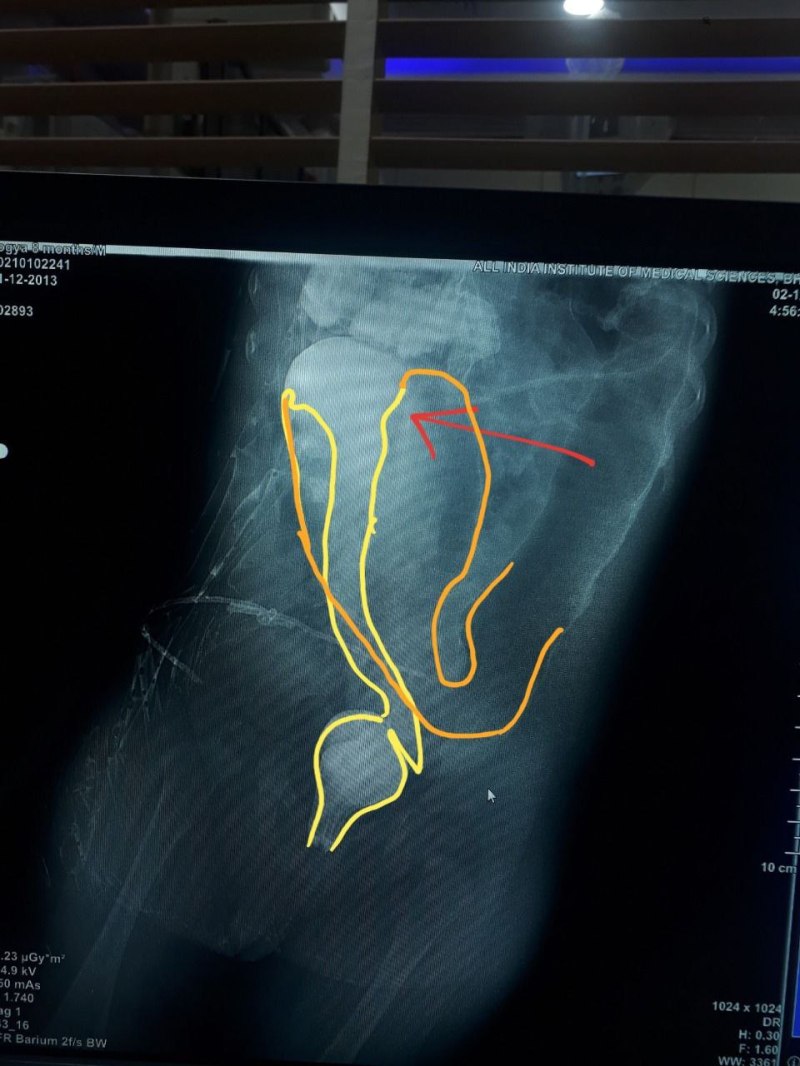

एम्स भोपाल हिर्शस्प्रुंग नाम की जटिल बीमारी से पीड़ित बच्चे का उपचार करने वाला पहला अस्पताल बन गया है। इसमें बच्चे के पेट पर बिना कोई चीरफाड़ किए केवल एक सर्जरी (प्राइमरी ट्रांसएनल एंडोरेक्टल पुलथ्रू) की गई है। यह सर्जरी मल उत्सर्जन के मार्ग के प्राकृतिक पथ से की जाती है। इस रोग के उपचार के लिए पहले दो या तीन सर्जरी की जाती थीं। इस सर्जरी में डॉ.अमित गुप्ता (सह प्राध्यापक) के नेतृत्व में बाल्य सर्जनों की एक टीम शामिल रही।

6 माह के बच्चे को लंबे समय से कब्ज और पेट फूलने की शिकायत के चलते बहुत बीमार हालत में लाया गया था। विशेष जांच और रेडियोलॉजी विभाग के सहयोग से किए गए कंट्रास्ट एनीमा और पैथोलॉजी विभाग के सहयोग से रेक्टल बायोप्सी के बाद 9 माह की उम्र में उसका ऑपरेशन किया गया। डॉ. अमित गुप्ता इस प्रक्रिया से बारह ऐसे रोगियों का पहले भी उपचार कर चुके हैं। सर्जरी के 6 माह बाद बच्चा बिल्कुल स्वस्थ है। उसका वजन बढ़ने के साथ-साथ सामान्य विकास हो रहा है। डॉ. अमित गुप्ता ने कहा कि इसमें पेट पर कट लगाने की कोई जरूरत नहीं होती है। पूरा ऑपरेशन प्राकृतिक मल उत्सर्जन मार्ग के माध्यम से किया जाता है। इस तरह की एक और सर्जरी इसके तीन महीने बाद की गई थी। इस तरह से एम्स में प्राथमिक टीईआरपी प्रक्रियाओं की कुल संख्या बढ़कर 2 हो गई है। दूसरे बच्चे में जन्म के तुरंत बाद इसके लक्षणों को देखा गया, ऐसे में 3 महीने की उम्र में उसका ऑपरेशन किया गया।